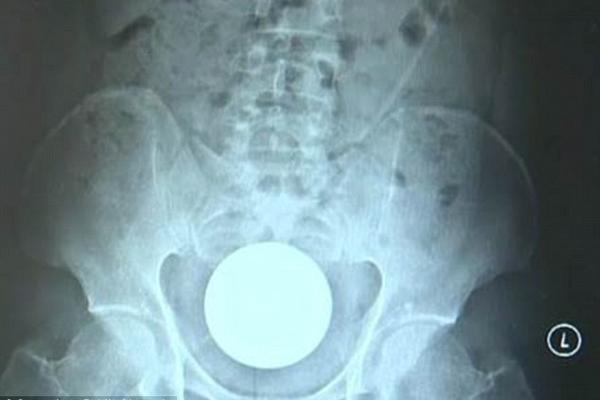

SVAKE GODINE 4000 LJUDI ZAVRŠI U BOLNICI ZBOG PREDMETA U OVOM DELU TELA: Ljudi u ŠOKU, evo koji POL to najviše RADI

DOKTORI SU BILI FRAPIRANI kad su pogledali ovaj RENDGENSKI SNIMAK!